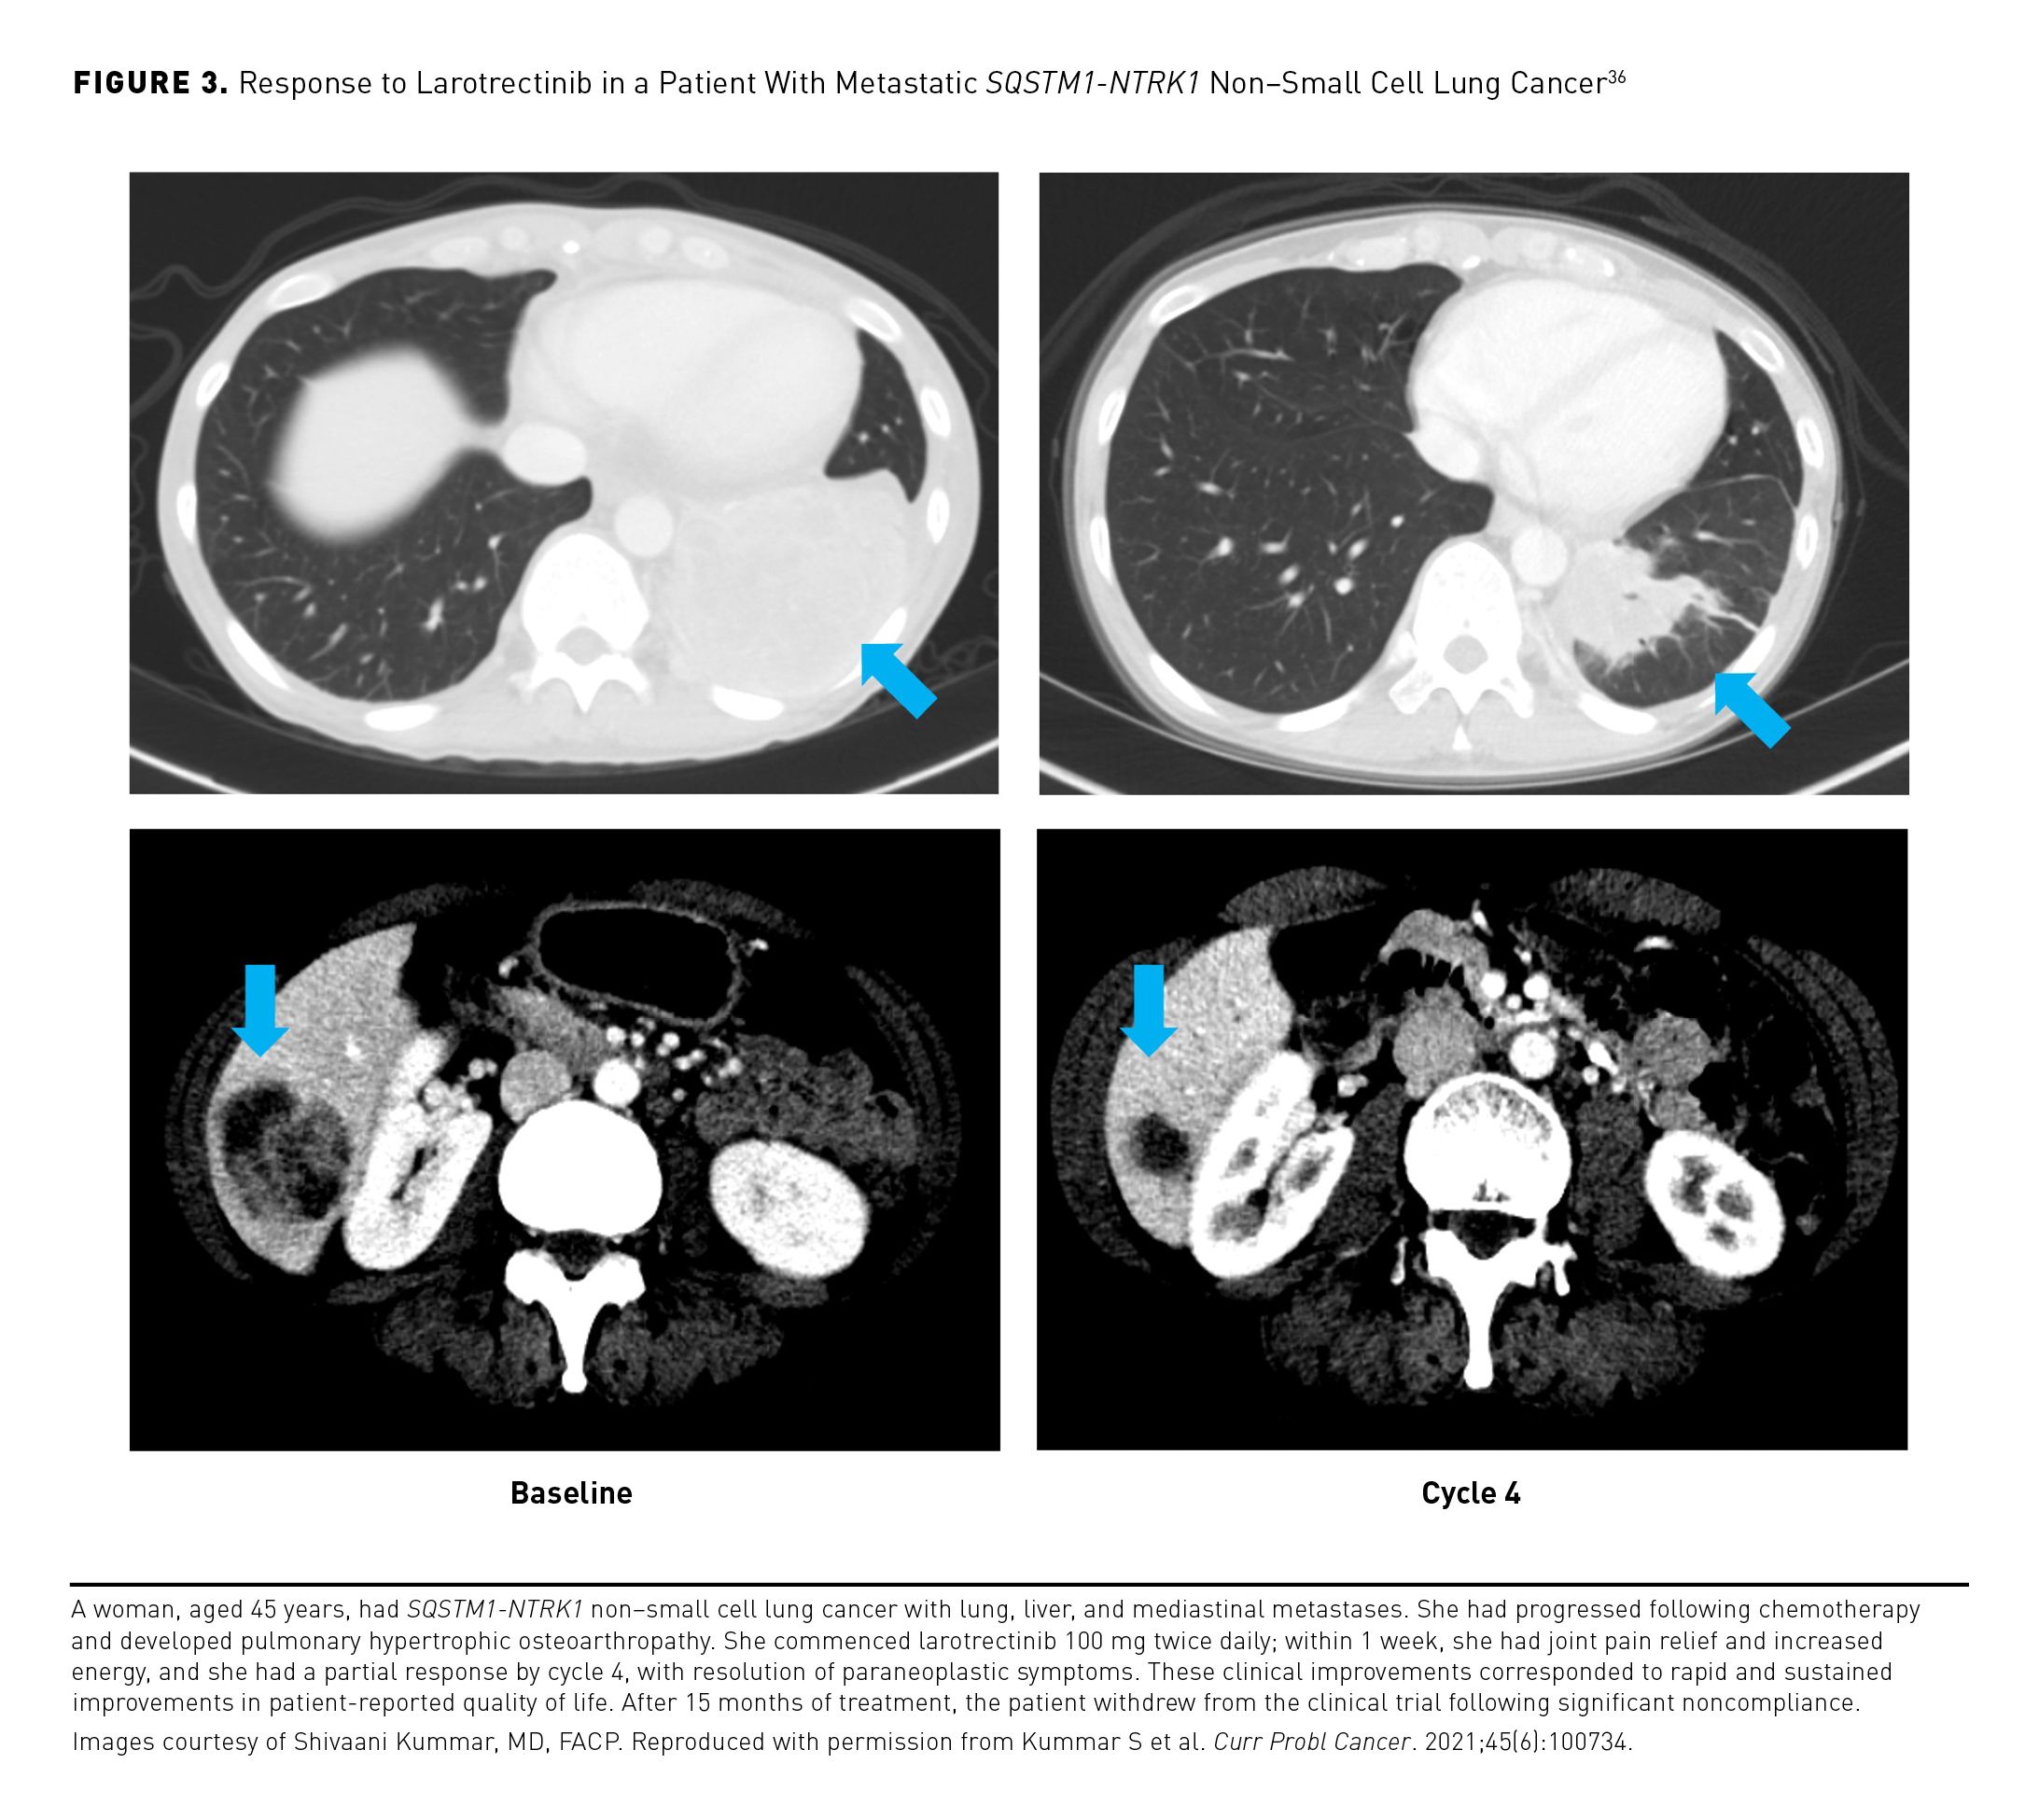

The larotrectinib clinical development program is unique, as it encompassed patients across the age spectrum, including children aged as young as 1 month, and with a wide range of tumor types. The efficacy and safety of larotrectinib was evaluated in 3 phase 1/2 clinical studies in adults and children with TRK fusion cancer, who received doses of 100 mg (adults) or 100 mg/m2 (children) twice daily; these were an adult phase 1 study (NCT02122913) and the SCOUT (NCT02637687) and NAVIGATE (NCT02576431) trials.30,34 The objective response rate (ORR) from a pooled analysis of these 3 studies (N=55) was 75% (95% CI, 61%-85%) per independent review and 80% (95% CI, 67%-90%) per investigator assessment, with responses seen regardless of age, tumor type, specific NTRK gene, or fusion partner. At 1 year, 71% of the responses were ongoing and 55% of patients were progression free. The majority of AEs were grade 1/2, and there were no treatment discontinuations due to AEs.30 In an expanded data set of 218 patients with TRK fusion cancer, the investigator-assessed ORR was 75% (95% CI, 68%-81%)(Table 3),28,29 and median duration of response (DOR) was 49.3 months (95% CI, 27.3 to not estimable [NE]).35 Median progression-free survival (PFS) was 35.4 months (95% CI, 23.4-55.7), and median overall survival (OS) was not reached.35 Responses were seen with larotrectinib across the spectrum of tumor types included in the study (Figure 2A).35 The clinical benefits of larotrectinib are illustrated in Figure 336 and Figure 4. Treatment-related AEs (TRAEs) observed in larotrectinib clinical trials were predominantly of grade 1/2; grade 3/4 TRAEs were reported in 18% of patients, the most common of which were decreased neutrophil count (7%), increased alanine aminotransferase (3%), and increased aspartate aminotransferase (2%).

Patients across the age spectrum—from infants to the elderly—who received larotrectinib experienced rapid, sustained, and clinically meaningful improvements in quality of life (QOL); these improvements began within 2 months in more than two-thirds of patients.36,37 QOL scores for most patients were either maintained within or moved into the normal healthy range during larotrectinib treatment.36 Among patients with TRK fusion cancer who had QOL below normal at baseline and were treated with larotrectinib, 91% of adults and 67% of children 2 years or older moved into the normal/above-normal QOL range following treatment.37 Sustained QOL improvements occurred within 2 months in 69% of adults and 75% of children 2 years or older and were maintained for a median duration of 12.0 months (range, 1.7-20.3) and NE (range, 1.1-23.0), respectively. With improving survival rates and increasing long-term treatment, patient-reported QOL is a particularly relevant goal to strive for, allowing patients to live both longer and better.